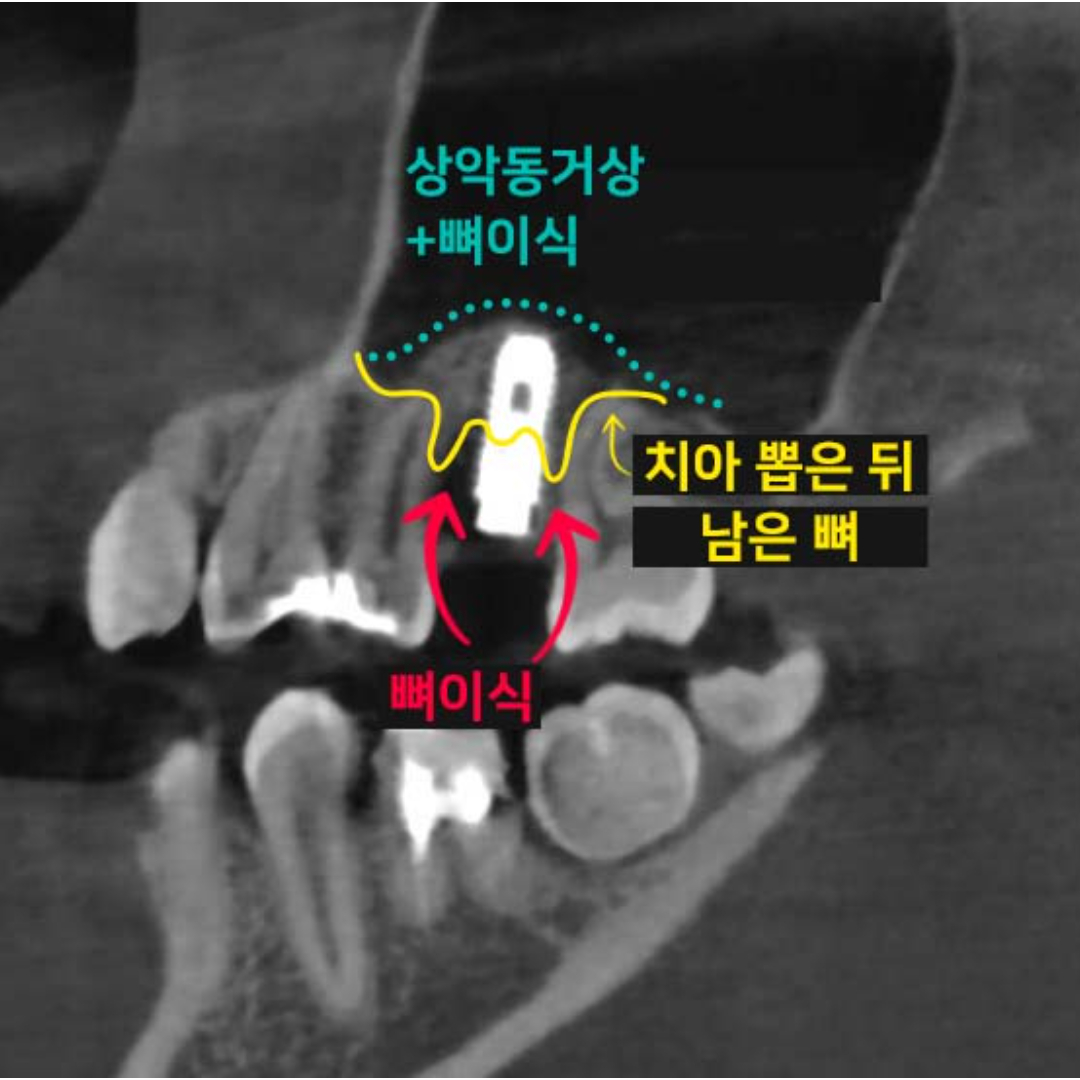

- 상악동 수술

- 부족한 잇몸뼈도 문제없다: 정교한 상악동 임플란트

- 상악동 수술

- 부족한 잇몸뼈도 문제없다: 정교한 상악동 임플란트